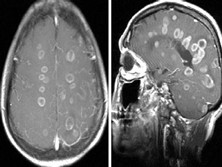

脑寄生虫病

脑寄生虫病是一种由寄生虫体、卵或幼虫侵入大脑引起的过敏性炎症、内芽肿形成或脑血管...

血常规、脑脊液检测、头部MRI、头部CT、X线平片、粪便检测

脑囊虫病、脑脓肿